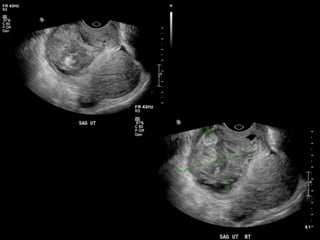

HISTORY

โ€ข 40 yo female 8.5 weeks pregant

โ€ข S/P D&C for pregnancy implanted at site of

c-section scar

โ€ข 6 weeks post D&C patient presents with

heavy persistent bleeding

โ€ข For Pelvic US

โ€ข HCG = 451 mIU/mL

HISTORY โ€ข 40 yofemale 8.5 weeks pregant โ€ข S/P D&C for pregnancy implanted at site of c-section scar

• 42.

โ€ข 6 weekspost D&C patient presents with heavy persistent bleeding โ€ข For Pelvic US โ€ข HCG = 451 mIU/mL